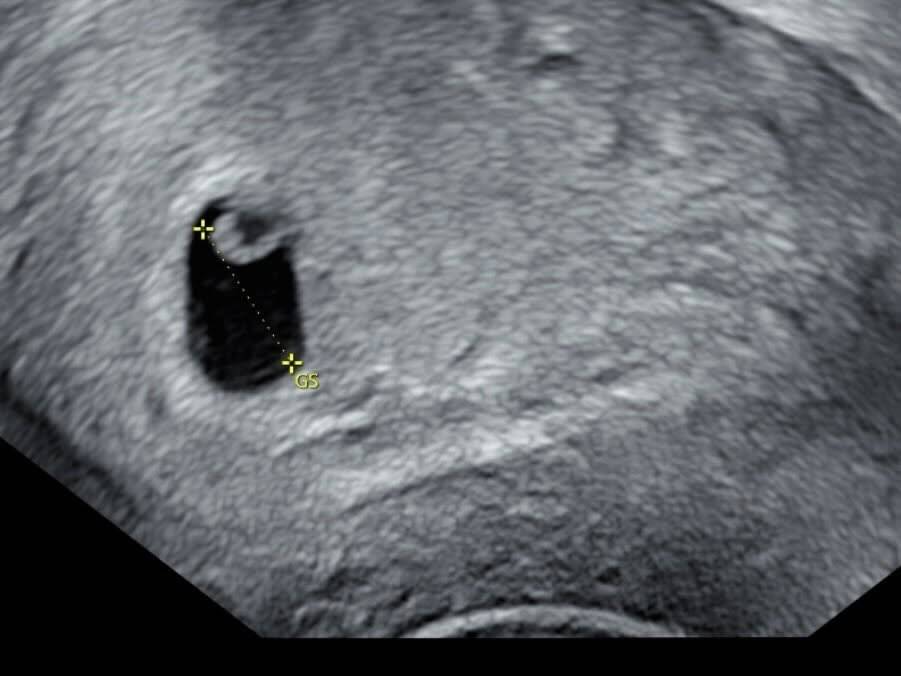

鄭家純在文中詳細描述了流產的痛苦經歷,令人心疼不已。她透露半個月前產檢時已發現胚囊發育遲了一周,當時醫生表示可能是排卵期延誤,亦可能是胚胎有狀況。直至昨晚(6日)傍晚,她開始出現少量出血,兩小時後出血量急增並開始腹痛,立即趕往急診求醫。在醫院期間,她陸續排出血塊,經陰道超聲波檢查後確認胎囊大小與半個月前產檢時相同,證實胚胎已停止發育。